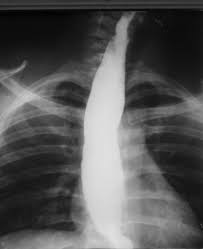

La evaluación de la acalasia se realiza mediante diversas técnicas de imagen y pruebas funcionales que permiten caracterizar la alteración de la motilidad esofágica y confirmar el diagnóstico. En primer lugar, las radiografías de tórax pueden mostrar niveles de aire y líquido en el esófago dilatado y lleno de líquido, lo que es indicativo de la incapacidad del esófago para vaciarse adecuadamente, una característica distintiva de esta enfermedad. Sin embargo, el hallazgo más característico y específico de la acalasia se obtiene mediante la esofagografía con bario, que revela una serie de signos típicos. Esta técnica permite visualizar la dilatación del esófago, la pérdida de la peristalsis esofágica, un vaciamiento esofágico ineficaz y el estrechamiento simétrico en forma de «pico de ave» en la porción distal del esófago, lo que refleja la incapacidad del esfínter esofágico inferior para relajarse correctamente. Esta imagen radiológica es fundamental para el diagnóstico inicial de la acalasia.

La esofagografía con bario se considera una herramienta sensible para diferenciar la acalasia de otras causas de disfagia. En este contexto, se ha demostrado que si, cinco minutos después de la ingestión de 240 mililitros de bario, la altura de la columna esofágica excede los 2 centímetros, la sensibilidad y especificidad de este hallazgo son mayores al 85% para diferenciar la acalasia de otras patologías esofágicas. A medida que la enfermedad progresa sin tratamiento, el esófago puede volverse significativamente dilatado, dando lugar a lo que se conoce como «esófago sigmoideo», una dilatación marcada en forma de S del esófago que se debe a la acumulación crónica de alimentos y líquidos debido a la disfunción del esfínter esofágico inferior.